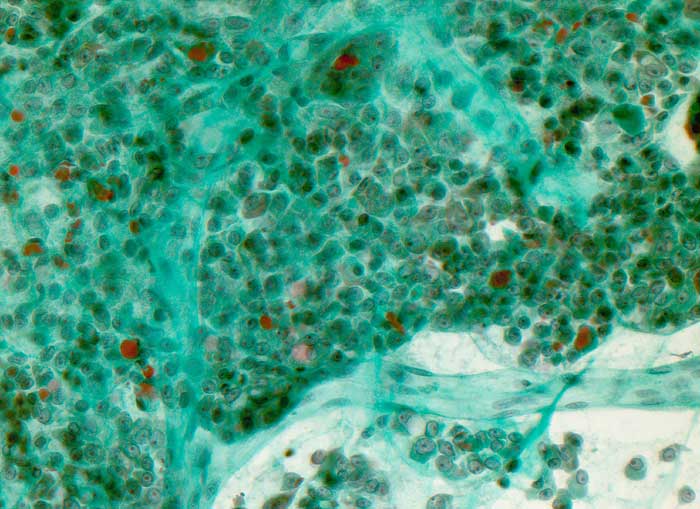

p/ Onkozytäres Schilddrüsenkarzinom

Onkozytäres Schilddrüsenkarzinom

Ausgeprägte Kernpolymorphie, Nukleolenatypie und unscharfe Zytoplasmagrenzen der oxyphilen Zellen sind Malignitätszeichen. Eine Unterscheidung von onkozytären Adenomen und Karzinomen ist zytologisch aber nicht sicher möglich.

Gezeigt werden zwei Fälle von histologisch gesicherten onkozytären Karzinomen.